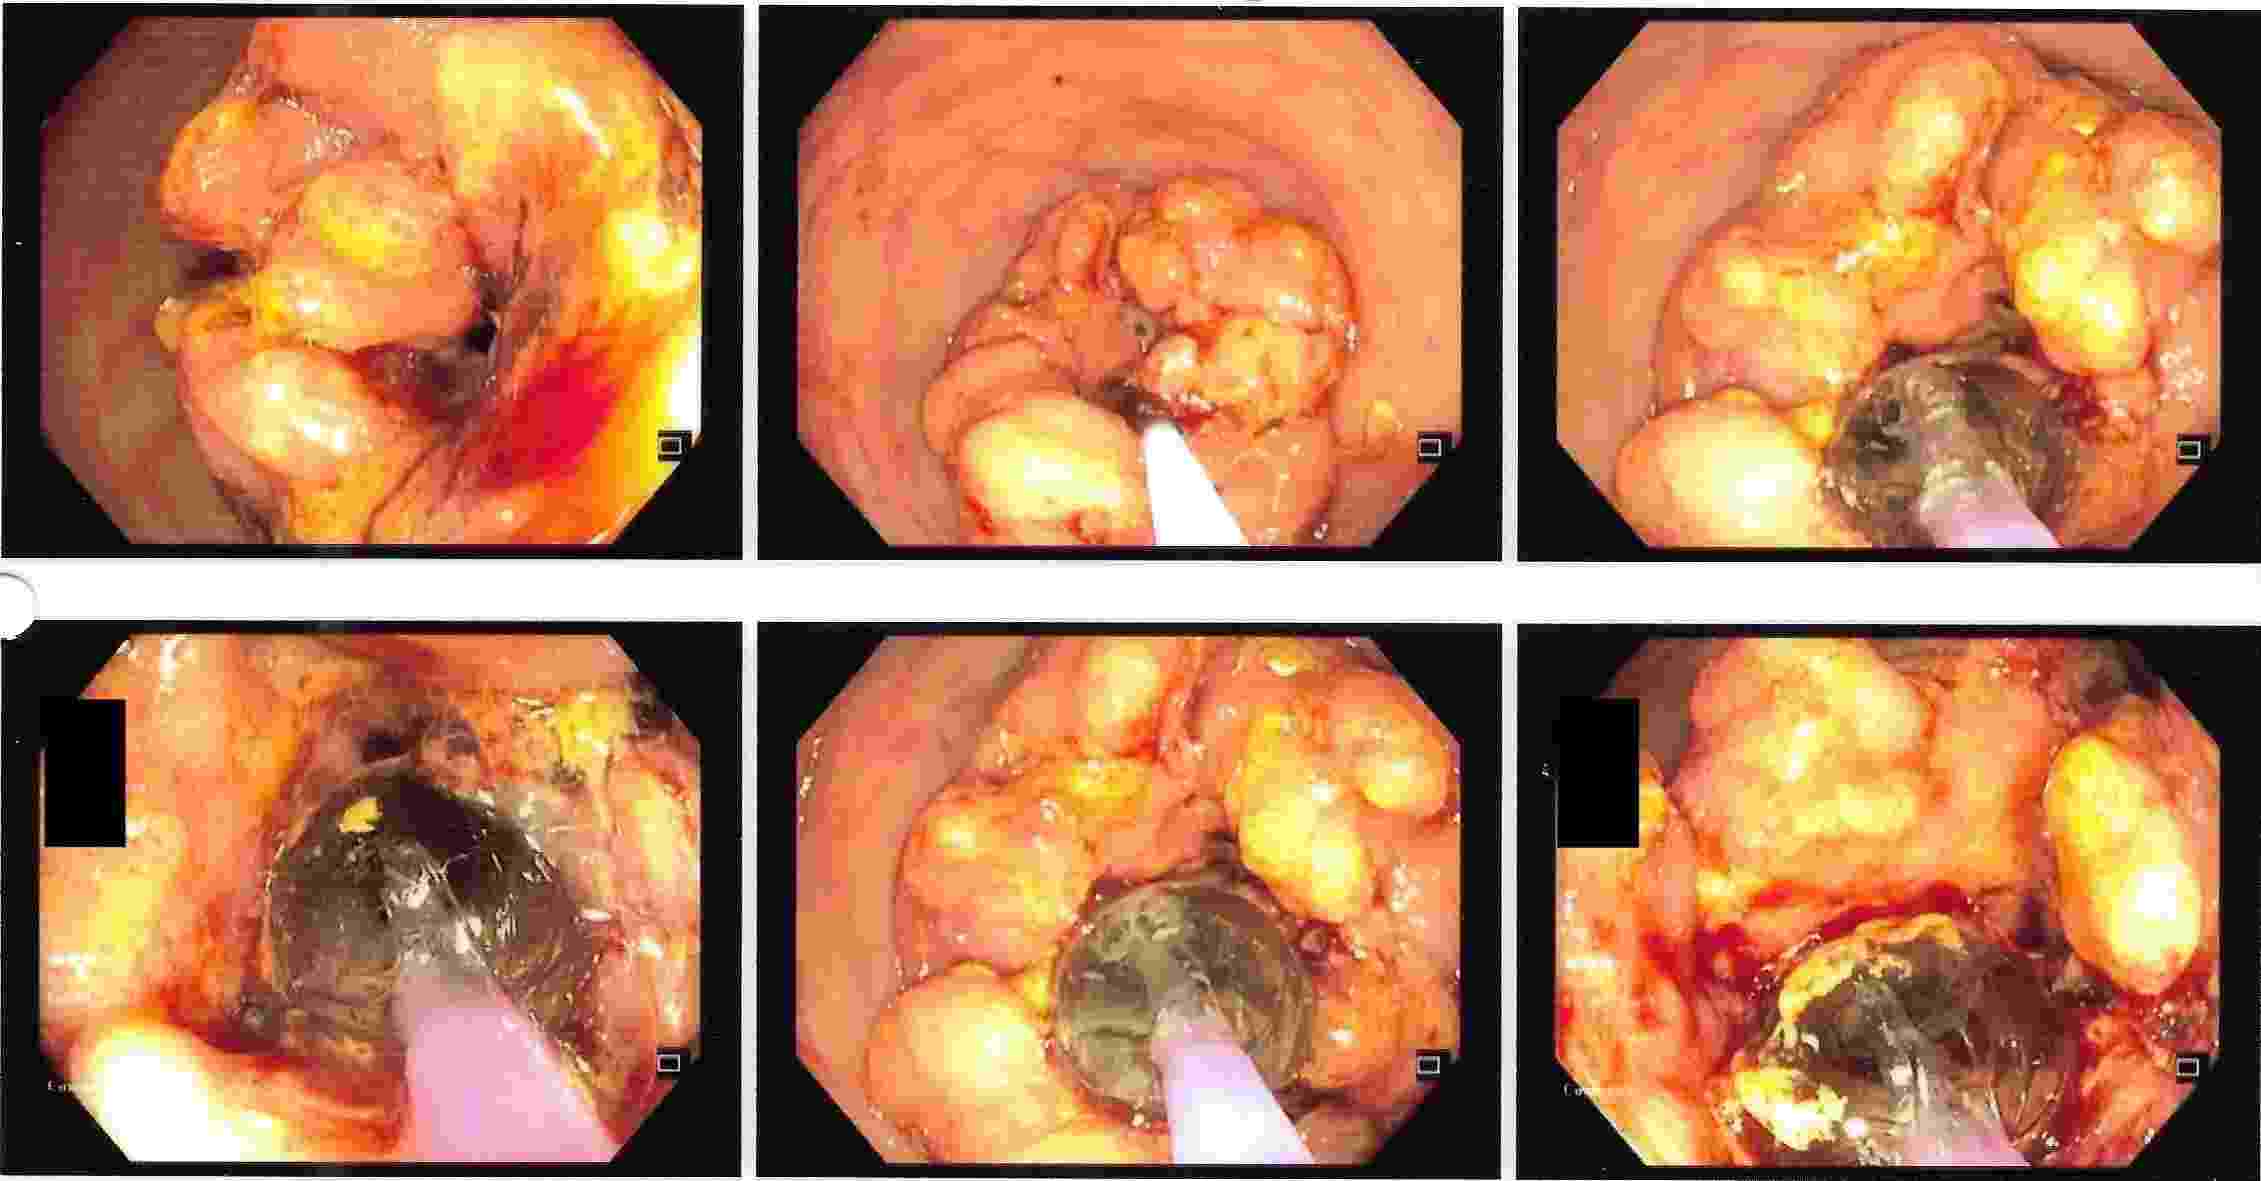

6. Foreign Body impaction can be dangerous especially with sharp objects alkaline batteries etc.

Foreign Body Impaction

GALL BLADDER STONES TREATMENT

Endoscopic Retrograde Cholangio Pancreatography is an advanced endoscopic procedure related to

diseases of pancreas and biliary tree. Common indication for ERCP is jaundice due to obstruction

of biliary tube, which drains the bile from the liver into the intestine.

Obstruction can be due to a gallstone, which has slipped into bile tube and has blocked the bile tube.

These Stones can be removed by ERCP, without any surgery being involved.

This procedure is necessary if the patient has stones in the gallbladder and also in bile tube and

is always performed before Laparoscopic removal of gallbladder. Cancer of the gallbladder, biliary tree, pancreas,

duodenum or obstruction by lymph nodes can be responsible for jaundice and can be very effectively

treated by ERCP without any need for surgery.

This technique is important in these conditions as majority of the patients coming for jaundice are at an advanced stage of cancer and need palliative treatment to give relief from severe itching and jaundice. Infection or narrowing in the biliary tree can be treated by ERCP.

Common Biles Duct Stones

Common Biles Duct Stones

Cancer of the Bile Tube in Duodenum

Impacted Stone in Common Bile Duct